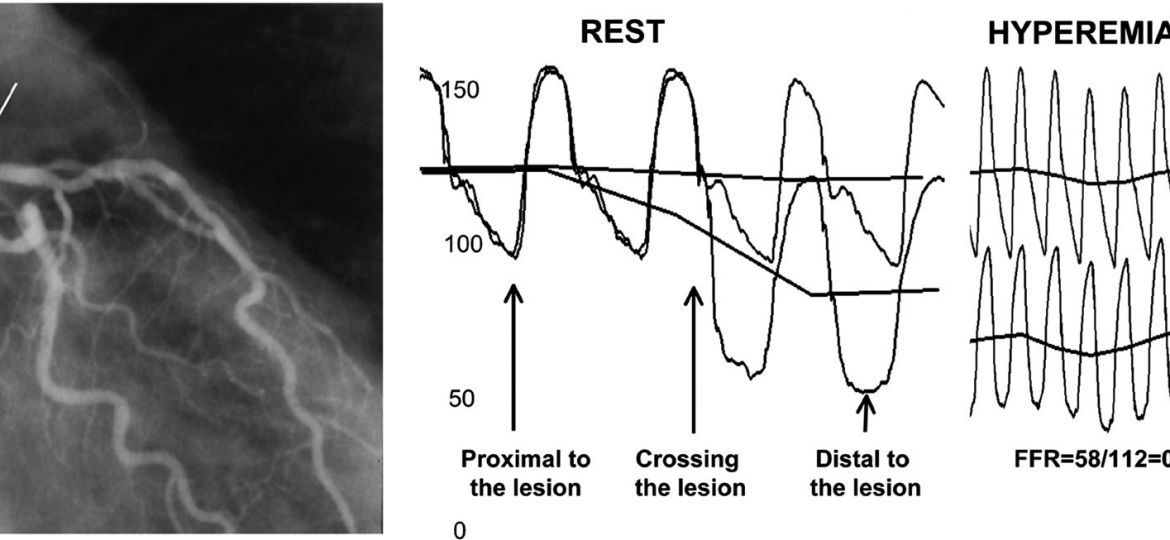

A síndrome coronariana aguda pode se apresentar de diversas e variáveis formas, dentre as quais a controversa síndrome Y…

A síndrome X cardíaca constitui uma entidade clínica semelhante a angina do peito, onde há isquemia miocárdica, porém com coronárias…